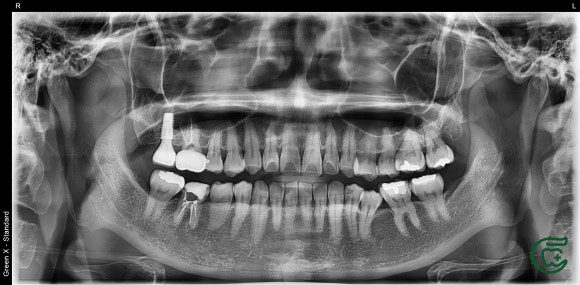

20250122

최종적으로 두 어금니 모두 건강한 상태로 확인된 후, 크라운을 이용한 최종 수복 작업을 진행했습니다.

이 사례는 단순한 치료 성공을 넘어,

무분별한 임플란트 시술 대신 자연치를 보존하는 것이 얼마나 중요한지를 다시 한 번 일깨워줍니다.